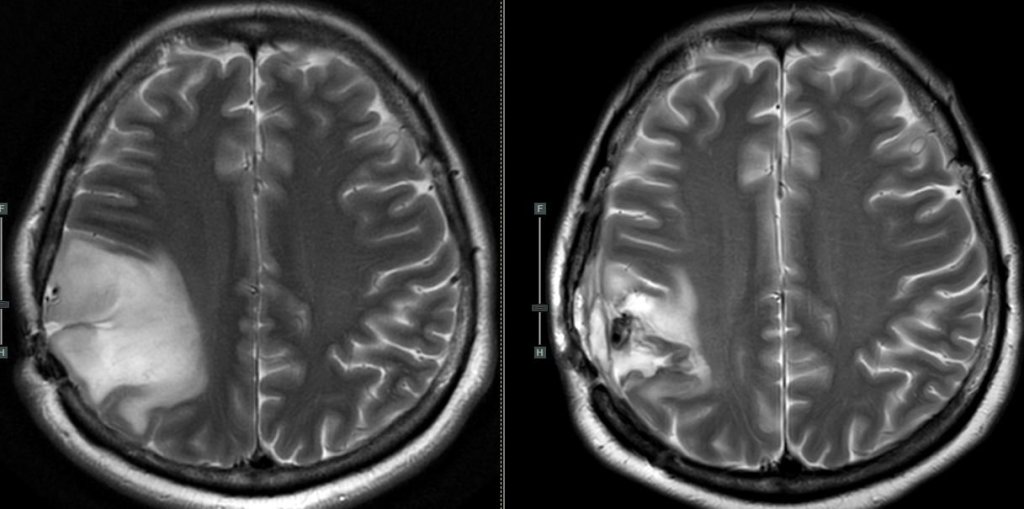

ผู้ป่วยรายนี้เป็นเนื้องอกชนิดกลีโอมา (glioma) ของสมองซีกขวา ได้รับการผ่าตัดแบบตื่นรู้ตัวเพื่อรักษาการทำงานของสมองซีกขวา (ซึ่งจะถือว่า “สำคัญ” ไหม ผู้อ่านคงต้องตัดสินใจเองนะครับ) หลังผ่าตัดช่วงแรกแม้จะมีอาการไม่ใส่ใจโลกข้างซ้ายเมื่อมีสิ่งกระตุ้นทั้ง 2 ข้าง แต่เนื่องจากเราเก็บการทำงานของสมองส่วนใหญ่ไว้ได้ ผู้ป่วยค่อยๆมีอาการดีขึ้นชัดเจนในเวลาต่อมา (ในขณะที่หากเราตัดเนื้องอกออกไปมากกว่านี้แค่ไม่กี่ CC ผู้ป่วยอาจจะเสียความใส่ใจนี้ไปแบบถาวรเลย)